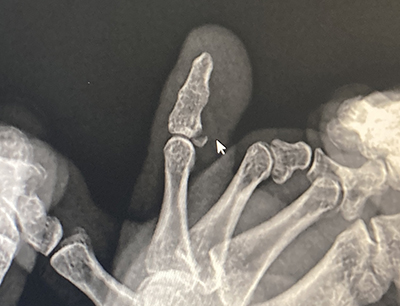

- 뼈가 사선으로 부러진 경우: 이 경우 깁스만으로는 충분한 고정이 되지 않으므로 수술이 필요할 수 있습니다.

- 압박골절로 조각이 많이 발생한 경우: 많은 골조각이 발생한 경우, 수술을 통해 정확한 정렬과 고정이 필요합니다.

- 개방성골절로 뼈가 근육과 살을 찢고 튀어나온 경우: 이러한 심각한 골절은 수술적 치료가 필수입니다.